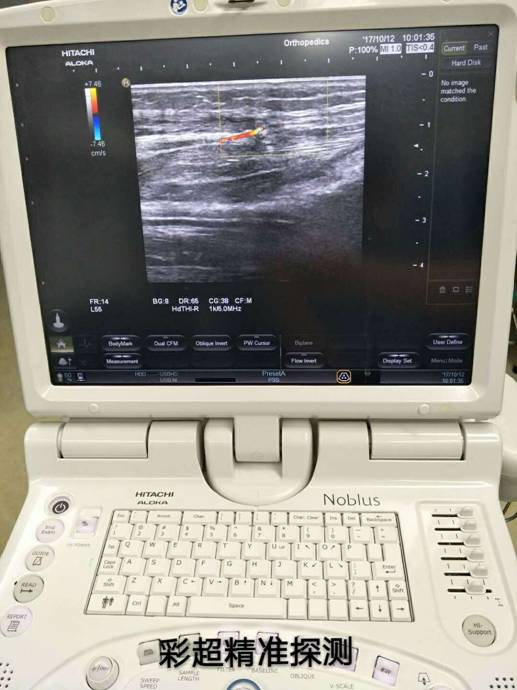

彩超定位精準(zhǔn)治療骨折修復(fù)皮瓣

訊員萬忠波、陳平國報(bào)道:粉碎性骨折+皮膚軟組織缺損+骨(肌腱)外露等損傷有了新療法,衡陽市中心醫(yī)院采用彩超精準(zhǔn)定位、多學(xué)科協(xié)作施術(shù),實(shí)現(xiàn)“大手術(shù)小創(chuàng)傷”。

近一個(gè)月來,衡陽市中心醫(yī)院收治了多位外傷導(dǎo)致小腿多處粉碎性骨折,小腿部分皮膚軟組織缺損、骨(肌腱)外露的患者,醫(yī)院燒傷整形科、骨科、超聲科多科協(xié)作,通過施行彩超定位下,小腿穿支皮瓣轉(zhuǎn)移修復(fù)創(chuàng)面手術(shù),均取得良好的手術(shù)效果,極大地減輕了患者的疼痛和創(chuàng)傷。

骨科根據(jù)患者骨折情況分別施行骨折復(fù)位+內(nèi)(外)固定術(shù),然后由燒傷整形科根據(jù)患者皮膚軟組織缺損情況,制定小腿穿支皮瓣轉(zhuǎn)移修復(fù)創(chuàng)面方案。為保證手術(shù)成功率,燒傷整形科會同超聲科由黃道遠(yuǎn)主任于術(shù)前利用彩超精準(zhǔn)的探測小腿術(shù)區(qū)的各個(gè)動脈穿刺,并逐一標(biāo)記,再由燒傷整形科手術(shù)團(tuán)隊(duì)根據(jù)動脈穿支的分布情況設(shè)計(jì)皮瓣,施行小腿穿支皮瓣轉(zhuǎn)移修復(fù)術(shù)。

由于采用了彩超定位技術(shù),使得皮瓣設(shè)計(jì)方案更合理,手術(shù)操作更精準(zhǔn),手術(shù)耗時(shí)更少,更因?yàn)楸Wo(hù)好了血管,術(shù)后皮瓣腫脹,存活均較以往有明顯改善,手術(shù)效果得到極大保障,患者滿意度大大提高。